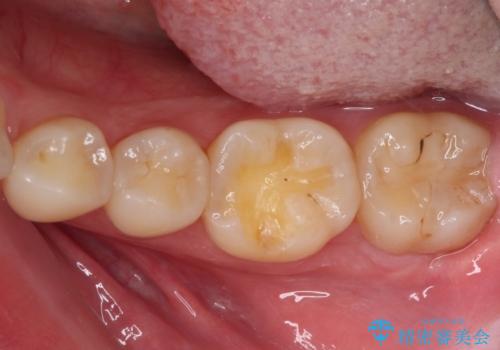

- 左下の奥歯が、冷たいものを食べるとしみて、舌で触るとザラザラすることが気になり来院された患者様です。

以前他院で治療したCR(樹脂の材料)が劣化し、その隙間から冷たいものがしみている可能性が高いことがわかりました。

嚙み合わせの力が強いため、再びCRやセラミックインレーによる修復を行っても割れてしまう可能性が高いので、

ゴールドインレーによる修復を行うこととしました。